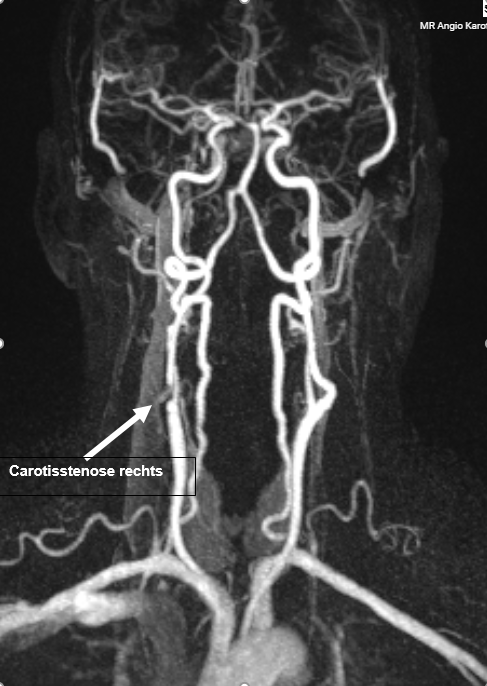

Das "große Bild": Eine dreidimensionale Darstellung des gesamten Gefäßbaums vom Hals bis tief in den Schädel – ganz ohne Röntgenstrahlungbelastung.

ℹ Der weiße Pfeil im Bild korreliert exakt mit dem Ultraschallbefund.